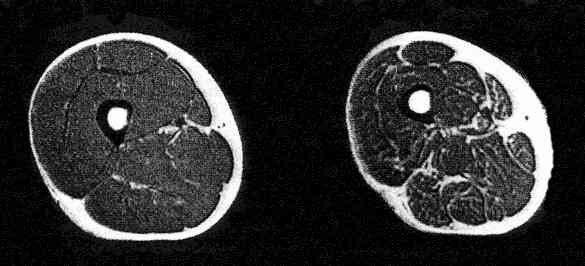

На фото предствлена нижняя конечность разных людей в сечении на МРТ. (Темные участки - мышцы, светлые - жир, светлый участок по середине - кость)